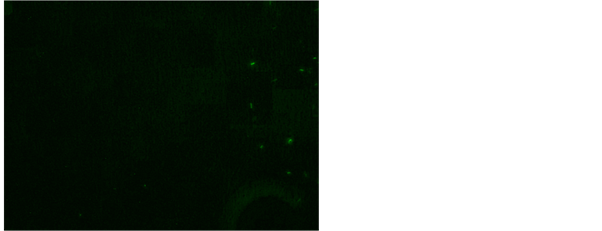

Study conducted by Krishnaswammi and Job in 1972 reported 102 (79.7%) sections positive for AFB on fluorescent technique, out of 128 lymph nodes with tuberculous histology. They used the Kuper and May (1960) method by using Auramine O and Rhodamine B [14] . Study conducted by Greenwood and Fox in 1973 shows 42 (60.0%) positive for AFB on fluorescent technique, out of 70 tuberculosis histology cases [15] . They applied the Mansfield (1970) method by using Auramine O and phenol. Study conducted by Rasool et al., in 2017 shows 54 (55.67%) positive for AFB fluorescent staining technique using Auramine O

and Rhodamine B [17] . Our study has revealed 56% positive for AFB after fluorescent staining in tissue biopsy and their touch preparations shows 54% positive for AFB after fluorescent staining (Figure 7 and Figure 8). This study shows

Figure 7. AFB in fluorescent stain Auramine O fluorescent stain using Auramine O and Rhodamine B, 200×.

Figure 8. AFB in rod, fragments and beads in and Rhodamine B, 200×.